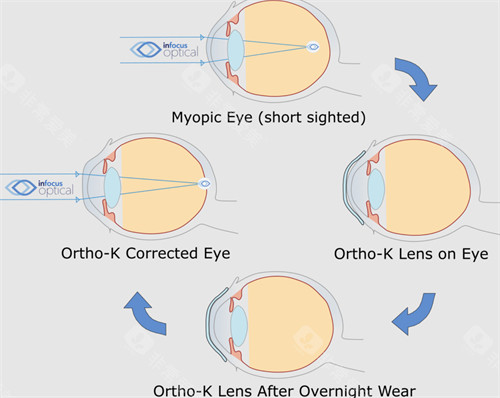

角膜病正规是科室的特色之一,对于各种角膜疾病,如角膜炎、角膜溃疡等,有着丰富的诊断和治疗经验。

此外,科室还开展了一些潮流的眼科手术技术,如飞秒激光辅助白内障手术等,大大提高了手术的可靠性和有效性。